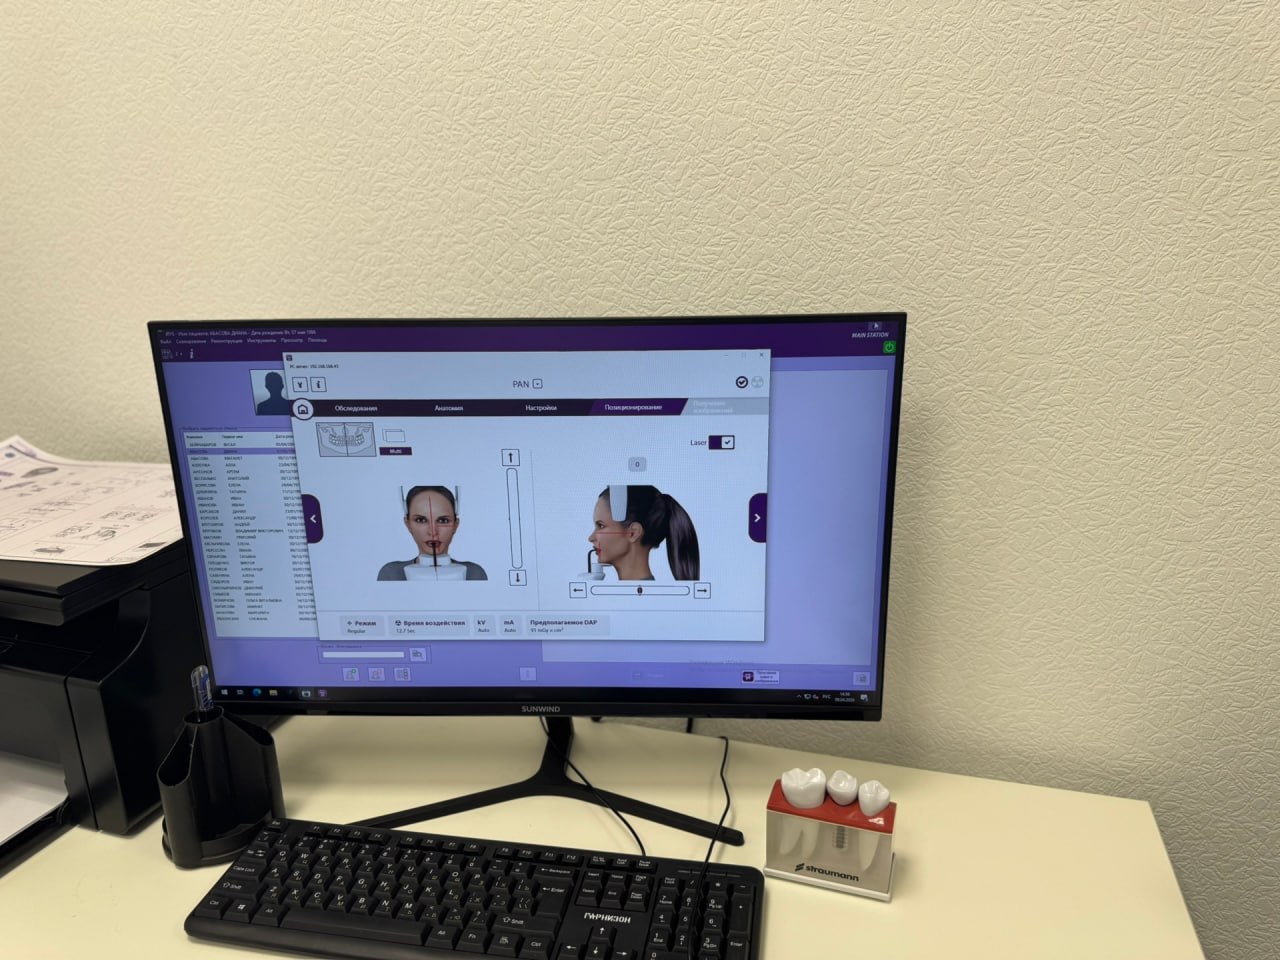

3D-моделирование результата до начала лечения

3D-моделирование результата до начала лечения